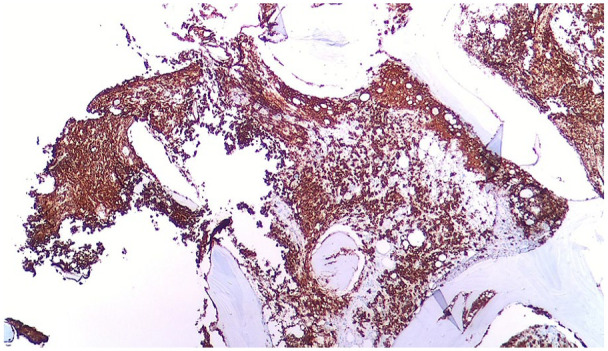

Abstract Image